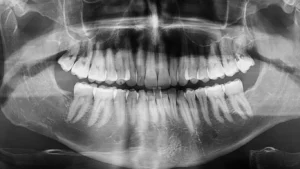

What is X-ray certification for dental assistants?

X-ray certification allows dental assistants to legally take dental radiographs under a dentist’s supervision. In Georgia, assistants must complete approved training in radiation health and safety to expose X-rays.

Radiography is a routine part of dental care, so most dental offices expect assistants to be trained before hiring.

Completing X-ray training improves job readiness and allows assistants to take on more clinical responsibility.